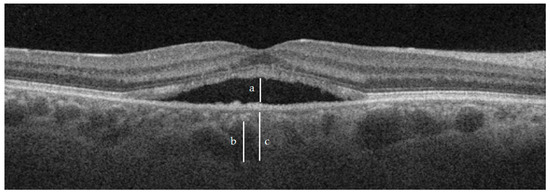

| CT | 374.9 ± 81.1 | 345.3 ± 71.5 | 0.0566 | 325.8 ± 59.2 | <0.05 | 280 ± 114.6 | <0.05 |

| Haller layer | 312.1 ± 71.3 | 287.4 ± 64.3 | 0.0953 | 274 ± 55.1 | <0.05 | 246 ± 115.9 | <0.05 |

| C-S | 62.8 ± 23.9 | 57.93 ± 20.8 | 0.3164 | 51.8 ± 18.3 | <0.05 | 34 ± 20.8 | <0.05 |